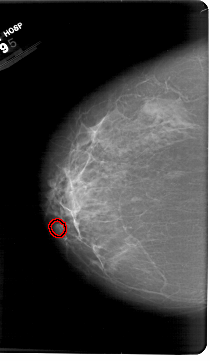

FILE: A_1386_1.LEFT_CC.OVERLAY

TOTAL_ABNORMALITIES 1

ABNORMALITY 1

LESION_TYPE CALCIFICATION TYPE AMORPHOUS DISTRIBUTION LINEAR

ASSESSMENT 4

SUBTLETY 1

PATHOLOGY BENIGN

TOTAL_OUTLINES 1

BOUNDARY

LEFT_CC LINES 6841 PIXELS_PER_LINE 3976 BITS_PER_PIXEL 12 RESOLUTION 43.5 OVERLAY